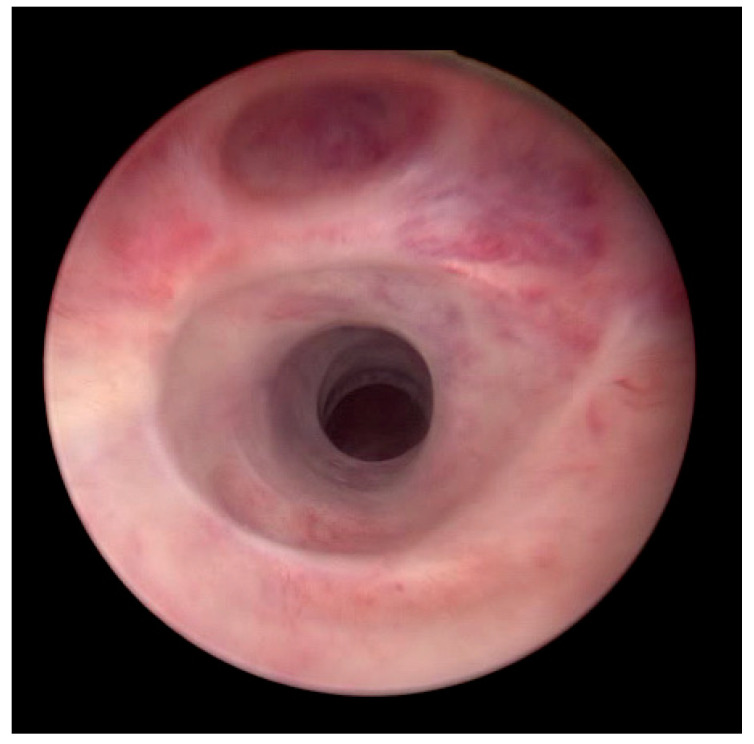

背景和目的:我们的目的是评估在复杂复发性尿道狭窄疾病治疗失败的患者中,前期Optilume药物包被球囊(DCB)扩张的结果。所有患者均出现急性尿潴留,无论狭窄部位和长度如何,均行DCB扩张治疗。材料和方法:我们回顾性评估急性尿潴留和已知复杂复发性尿道狭窄的患者。在2021年8月至2024年2月期间,无法排空或排空后残留(PVR)容量超过400ml的患者出现在我们三级中心的泌尿科急诊室。尿道造影和/或内窥镜成像证实了诊断。排除尿路感染/败血症患者和神经系统疾病患者。先行尿道扩张至20fr,然后行DCB扩张(30fr, 10bar, 10min)。主要终点是12个月时解剖成功(膀胱镜检查/校准≥14fr)和没有重复干预。结果:31例男性患者连续接受评估,其中26例随访≥12个月(平均年龄65±16.8岁)。狭窄部位包括球囊狭窄7个,球膜狭窄7个,吻合口狭窄7个,膀胱颈狭窄3个,阴茎狭窄1个,全尿道狭窄1个。既往尿道/手术干预的中位数为2例[IQR: 1-3](范围:1-31)。中位狭窄长度为3 [IQR: 2-4] cm(范围:1-8)。12个月时,65.4%(17/26)的患者手术成功,无复发和再手术。结论:对于复杂复发性尿道狭窄和尿潴留患者,特别是不能或不愿进行手术重建且不愿留置导尿管的患者,及时行DCB扩张可能是一种可行的治疗选择。

Background and Objectives: We aimed to assess the outcomes of upfront Optilume drug-coated balloon (DCB) dilation in patients after failed treatment for complex recurrent urethral stricture disease. All patients presented with acute urinary retention and were treated with DCB dilation regardless of stricture site and length. Materials and Methods: We retrospectively evaluated patients with acute urinary retention and known complex recurrent urethral strictures. Patients presented at the urology emergency room of our tertiary centre with an inability to void or a post-void residual (PVR) volume exceeding 400 mL between August 2021 and February 2024. Urethrography and/or endoscopic imaging confirmed the diagnosis. Patients with urinary tract infection/sepsis and those with neurological disease were excluded. Urethral dilation to 20 Fr was performed, followed by DCB dilation (30 Fr, 10 bar, 10 min). The primary endpoints were anatomical success (≥14 Fr by cystoscopy/calibration) at 12 months and freedom from repeat interventions. Results: Thirty-one consecutive male patients were evaluated, with twenty-six patients followed for ≥12 months (mean age 65 ± 16.8 years). The stricture sites included seven bulbopenile, seven bulbomembranous, seven anastomotic, three bladder neck, one penile, and one panurethral stricture. The median number of prior urethral/surgical interventions was 2 [IQR: 1-3] (range: 1-31). The median stricture length was 3 [IQR: 2-4] cm (range: 1-8). At 12 months, 65.4% (17/26) of subjects voided satisfactorily and were free of recurrence and reoperation. Conclusions: Timely DCB dilation may offer a viable treatment option for patients with complex recurrent urethral strictures and urinary retention, particularly those who are unable or unwilling to undergo surgical reconstruction and prefer to avoid indwelling catheters.